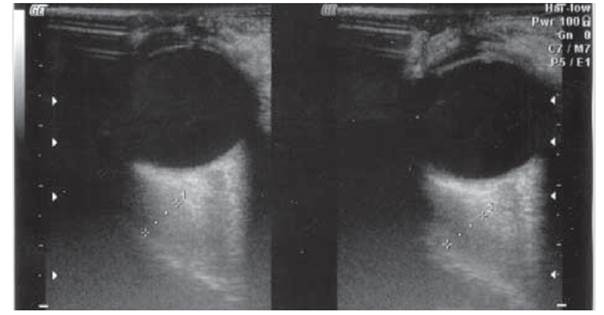

3.17 сурет. УДЗ мәліметтері бойынша эндокринді офтальмопатия кезінде дамыған көзқозғалтқыш бұлшықеттерінің жуандауы